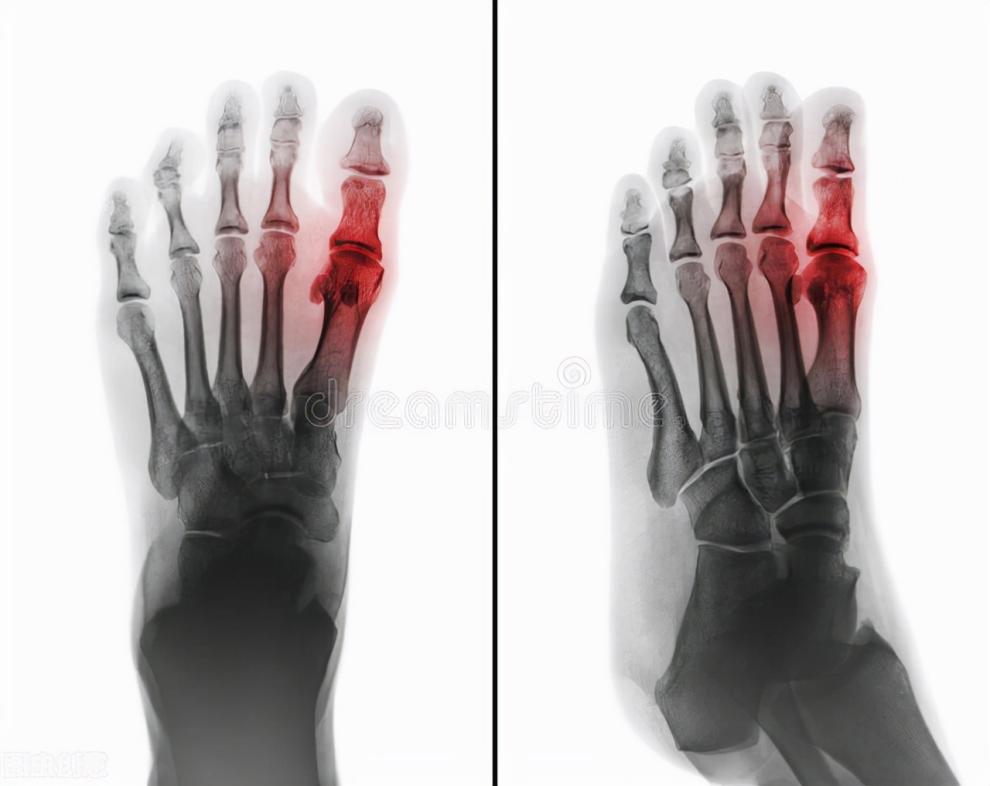

2、痛风性关节炎 它是由于尿酸盐沉积在关节软骨或关节滑膜上,引起关节周围组织出现炎症的一种关节炎,常起病于脚趾关节,多见于40-60岁的男性。主要表现为急性关节炎,常于夜间或者清晨突然发病,一般单侧发病,红肿、疼痛为主要症状。持续数天后可自行缓解,但很容易复发,而且发作间隔越来越短,发病的关节也越来越多。随着痛风石越积越大,受累的关节也逐渐变大、畸形、僵硬,最终影响关节正常功能。